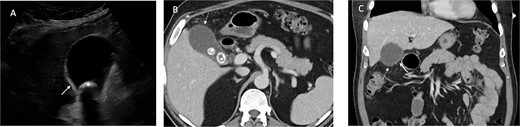

Contrast enhanced axial (A) and coronal (B) CT images in portal venous phase demonstrate periappendiceal abscesses (solid arrows) closely associated with thick-walled and inflamed tip of the appendix (dashed arrows). Note the normal appearing base of the appendix (arrowhead in A).